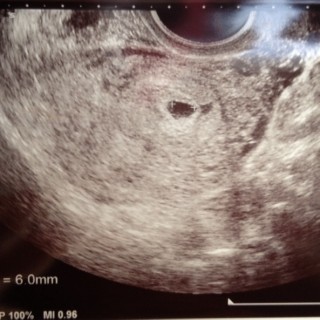

生理予定日から胃がムカムカしてきて期待しつつ一週間後に検査薬で陽性確認! 3ヶ月くらい前にクラミジアが発覚して子宮内が男性ホルモン多くて排卵しづらいと言われてたのですが、治療してからすぐに授かりました! 病院に行って胎嚢確認! 6mmの胎嚢のみ確認でした♪

初診で7ミリって言われました^_^

まだ小ちゃいけど無事に成長してくれますようにー(*^_^*)